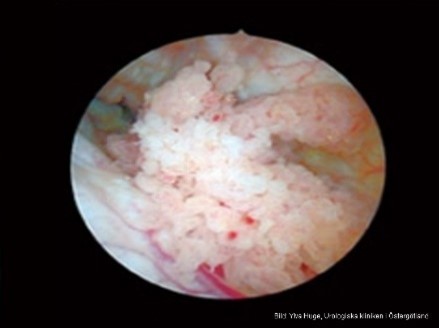

Vad är detta?

Cancer i urinblåsa (urotel)